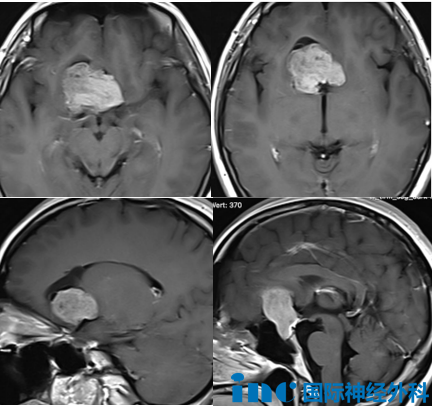

2025年10月,武女士的鼻子突然闻到一股陌生的味道(幻嗅),而后她开始头痛,还出现了癫痫。尽管在住院后已注射安定类药物,但武女士仍多次出现轻微抽搐症状。核磁显示,武女士的颅内存在一个巨大鞍区占位,约3.3cm×4.2cm×4.1cm,已致双侧大脑前动脉受压移位。

经过INC的积极协调,平安夜当天,在爱人和家人的注视下,武女士被推入手术室。实际上,这一次的手术关键在于鞍内部分——这里是肿瘤的起源位置,也是垂体和垂体柄所在的重要区域。这一点,巴教授早在术前就已告知:“这部分必须谨慎处理,以保护垂体功能不受影响。同时,肿瘤已累及大脑前动脉,血管保护至关重要。”